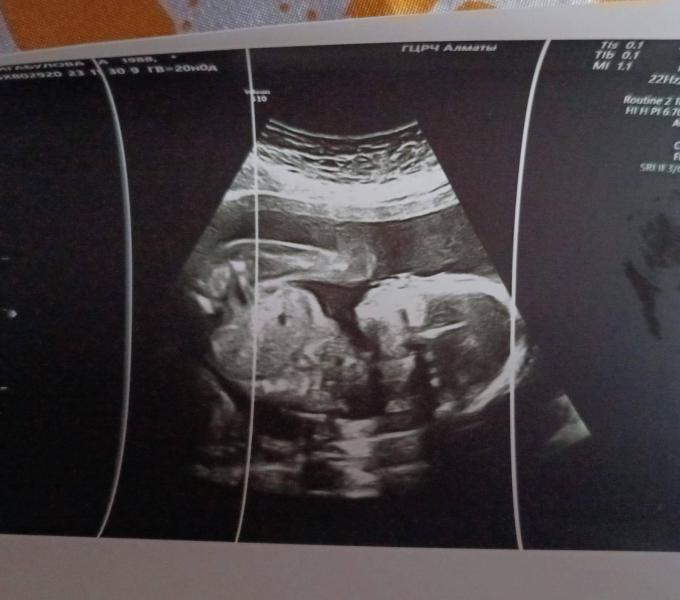

30.11 сходила на 2 скрининг.мне потвердили 100% девочку😁 даже фотку дали.была я у Тургумбаевой в ГЦРЧ 8 кабинет.8 декабря съездили к маме,сестре и сделала там гендер пати скромный по семейному🥰 шар который приготовила вручила маме, как раз на её день рождение 60 лет подарок😁 обрадовались все😁🥰 так что доча мы тебя ждем не дождемся❤️

Мне на 15 неделе ПО идее уже предположительно сказали доча будет ❤️ на втором скрининге (20 неделе) подтвердили девочку 🎊